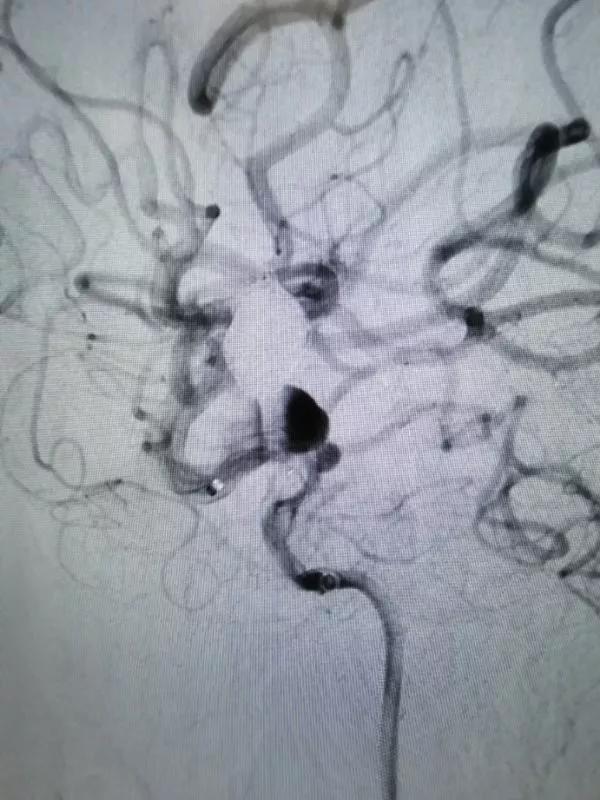

再行右侧颈内动脉血流导向装置置入术:将8F Envoy导引导管置入右侧颈总动脉,105cm 6F Navien导引导管头端置入颈内动脉岩骨段,造影见海绵窦段3个动脉瘤,由近及远直径一次为5mm、8mm、9mm,颈内动脉床突上段可见一大小约为5×4mm的宽颈动脉瘤。

DSA图像

然后再次通过支架并达到右侧大脑中动脉,向海绵窦段多发动脉瘤输送并释放4.0×30mm Tubridge®支架。

▲造影见造影剂滞留,载瘤动脉通畅。